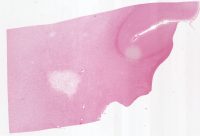

AANP2002-10.svs

58000 x 37369

@ 20X